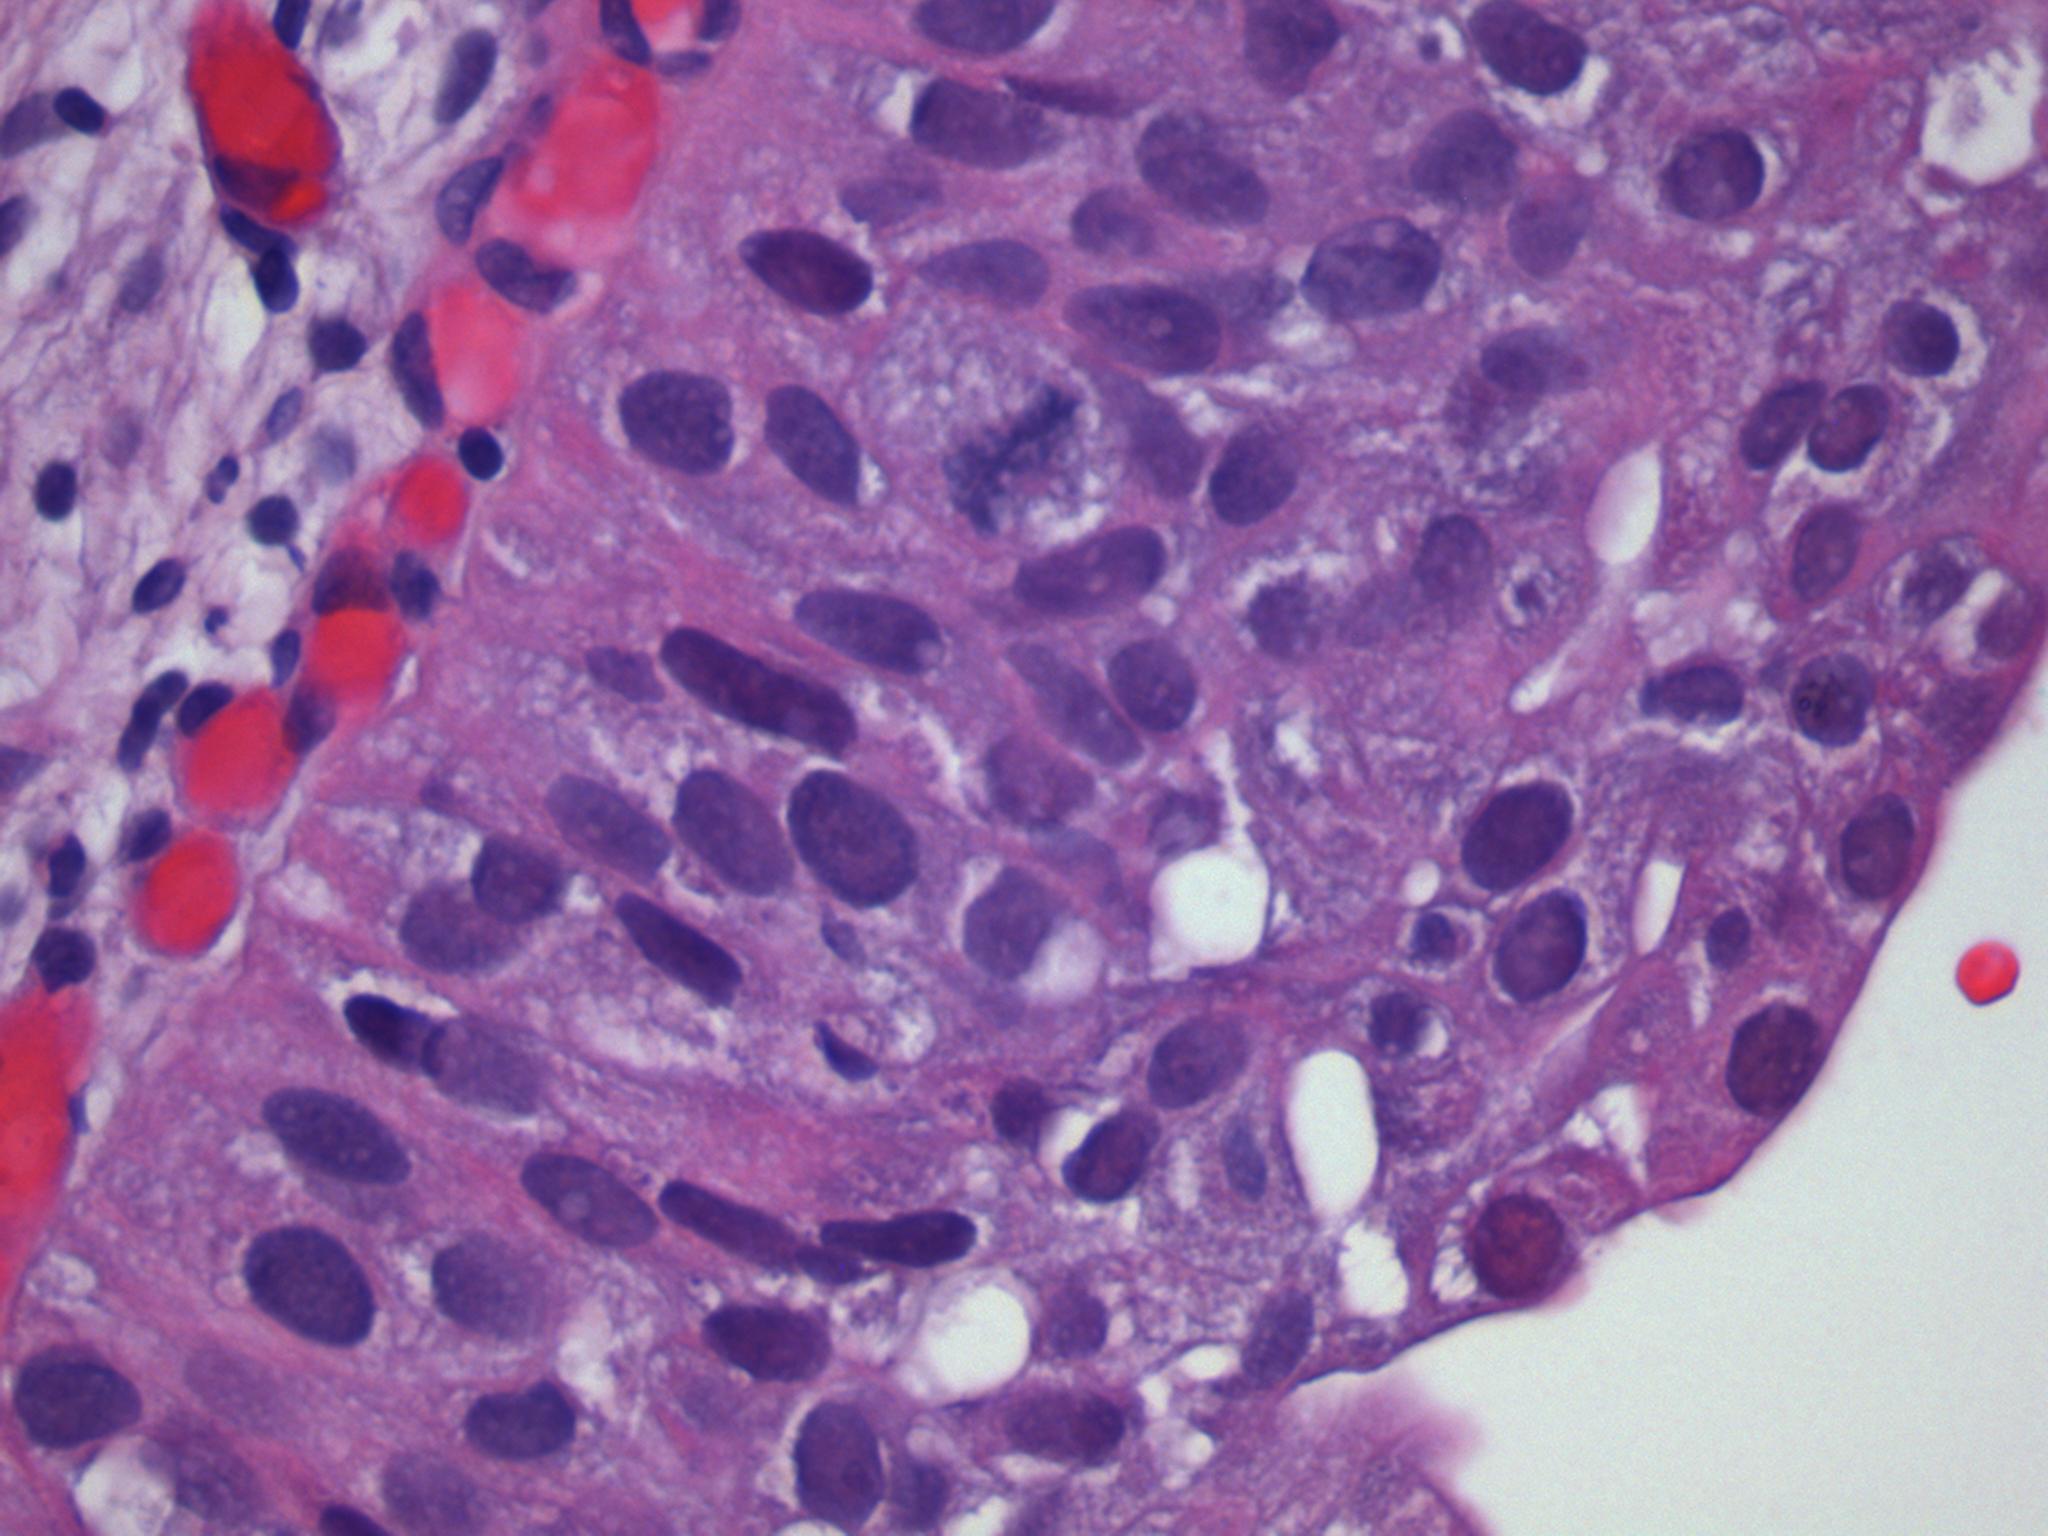

Consensus grade: Carcinoma in situ (CIS)

The urothelium displays loss of cohesion, loss of polarity and prominent pleomorphism.